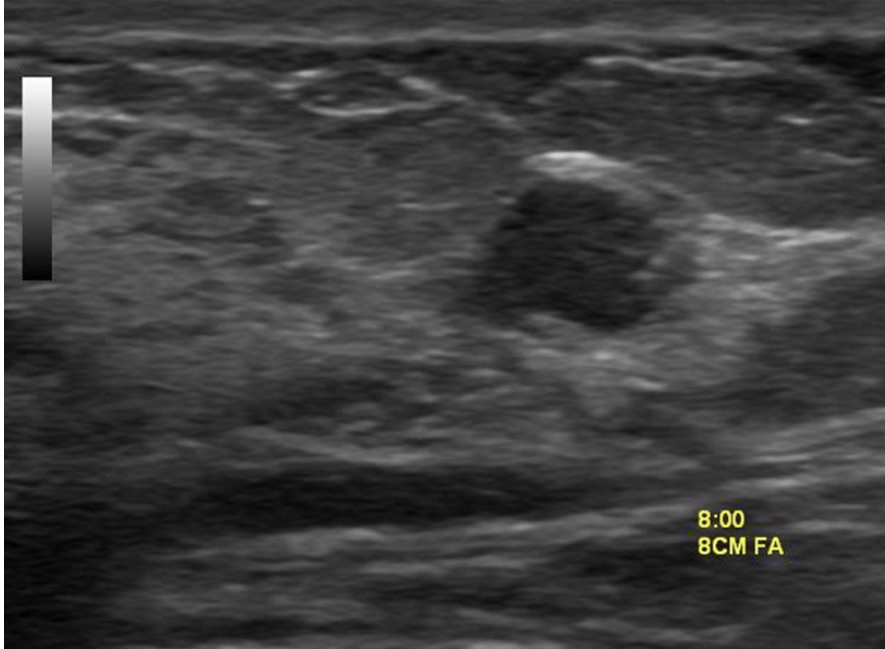

• The hypoechoic lesion in the image does not have smooth margins but appears microlobulated

• Regardless of whether the classification of Stavros or the American College of Radiology is used:

• The risk of the lesion in this patient is not low enough to be considered BIRADS 3 nor high enough risk to warrant BIRADS 5:

• Thus, it falls somewhere in the BIRADS 4 range:

• Biopsy is required